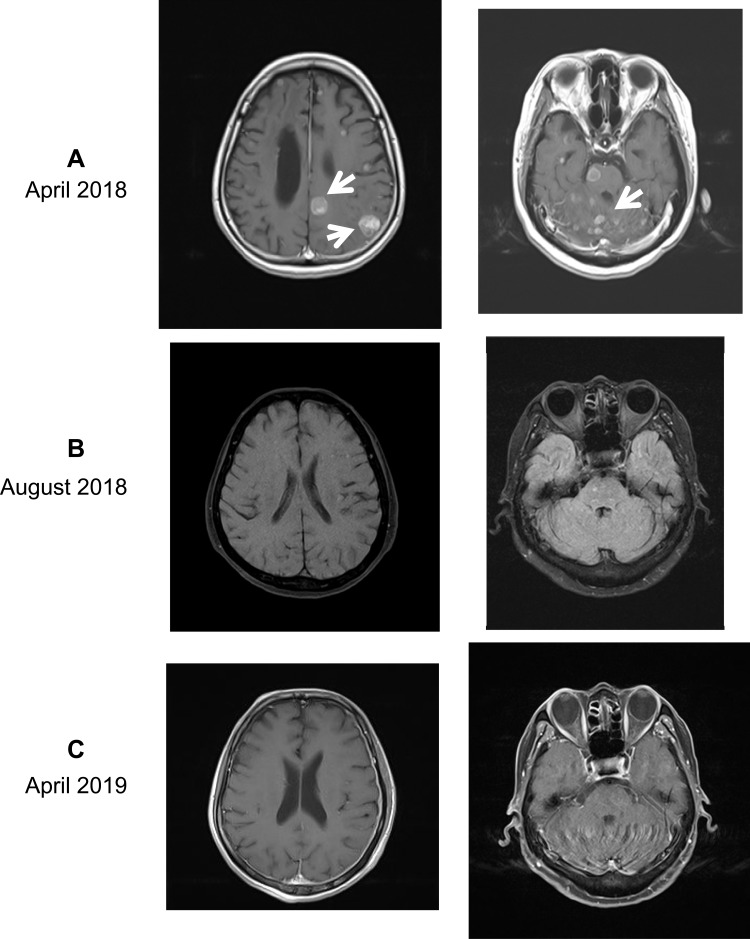

Przypadek 44-letniej pacjentki z rakiem płuc i przerzutami

W listopadzie 2015 roku u 44-letniej kobiety zdiagnozowano raka płuc z licznymi przerzutami. Obecność przerzutów odległych do narządów takich jak wątroba, kości czy nadnercza wskazuje na zaawansowane stadium choroby. Po usunięciu przerzutów do mózgu rozpoczęto leczenie lekami celowanymi podawanymi doustnie. Przez 28 miesięcy większość zmian była stabilna. Jednak w marcu 2018 roku wykryto nowe przerzuty w mózgu, wodogłowie w trzeciej komorze i komorach bocznych mózgu, a także przerzuty w kościach, nadnerczach i wątrobie.

Leczenie nowotworów z przerzutami do innych tkanek i narządów jest szczególnie trudne i wymaga stałego monitorowania nawrotów choroby. W kwietniu 2018 roku, z powodu braku skuteczności wcześniejszego leczenia, pacjentka rozpoczęła terapię wodorem w postaci gazu.

- Po 4 miesiącach – znaczące zmniejszenie guzów w mózgu

- Zmniejszenie wodogłowia w komorach mózgu

- Po roku – całkowity zanik guzów w mózgu

- Stabilizacja przerzutów w innych narządach

- Wydłużenie czasu przeżycia pacjentki

Po roku terapii wodorem wszystkie guzy w mózgu zniknęły, a przerzuty w wątrobie i płucach nie wykazywały znaczących zmian. Wyniki te sugerują, że po niepowodzeniu standardowego leczenia, terapia wodorem może być skuteczna w kontrolowaniu zmian nowotworowych, szczególnie w obrębie mózgu.

Opisany przypadek wskazuje, że wodór molekularny może stanowić wartościowe wsparcie terapeutyczne w zaawansowanych stadiach choroby nowotworowej, zwłaszcza jako uzupełnienie leczenia konwencjonalnego.